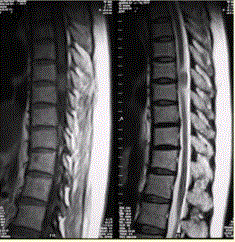

问题 患者女,52岁,颈部不适2年。MRI检查结果如下图。 病变的定性诊断为

选项 A.脊膜瘤 B.神经纤维瘤 C.神经鞘瘤 D.转移瘤 E.表皮样囊肿 F.血管瘤

答案 A

解析 A